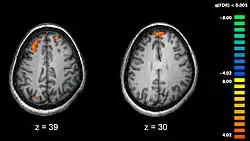

- Les gènes NOTCH4, NRG1 ou DTNBP1[29] : le gène DTNBP1 est un des gènes les plus susceptibles d'expliquer des cas de schizophrénies avec des résultats concordants plusieurs fois répliqués[69],[70],[71],[72],[73]. Les changements d'allèles de deux marqueurs de polymorphisme nucléotidique simple Rs1018381 et Rs2619522 sur le gène DTNBP1 impactent tous deux le volume de matière grise dans des régions du cerveau bien spécifiques[74]. On a pu révéler par IRM[75] que les porteurs de l'allèle G sur rs2619522 exhibaient un volume plus élevé de matière grise dans l'hippocampe, le cortex frontal et pariétal. Les porteurs de l'allèle T de rs1018381 possédaient une augmentation de volume dans les régions du lobule lingual et du thalamus. Les auteurs ont noté l'effet contre-intuitif de l'augmentation du volume de l'hippocampe, contraire à la réduction habituellement observée pour d'autres cas de schizophrénies. Environ 25 % des Européens possèdent l'allèle G du marqueur rs2619522 et environ 5 % sont homozygotes GG[76]. Quant à Rs1018381, environ 15 % des Européens possèdent l'allèle T et moins d'1 % sont homozygotes TT[77], ce qui prouve une faible sélection naturelle de ces génotypes dans cette population. Les individus portant un seul allèle à risque à la fois sur Rs1018381 et Rs2619522 posséderaient un endophénotype cérébral compromis particulièrement vulnérable pour développer un plus grand risque de schizophrénie.

Des études mettant en œuvre des tests neuropsychologiques combinés à des techniques d'imagerie cérébrale comme l'imagerie par résonance magnétique fonctionnelle (IRMf) ou la tomographie par émission de positons (TEP) ont cherché à mettre en évidence des différences fonctionnelles d'activité cérébrale chez des patients. Elles ont montré que ces différences surviennent plus fréquemment au niveau des lobes frontaux, de l'hippocampe et des lobes temporaux[163]. Ces différences sont fortement liées aux déficits cognitifs fréquemment associés à la schizophrénie, notamment dans le domaine de la mémoire, de l'attention, de la résolution de problèmes, des fonctions exécutives et de la cognition sociale.